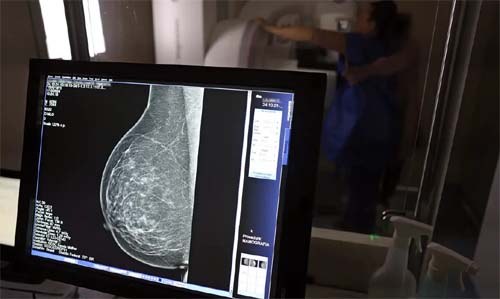

Direitos Previdenciários para Mulheres com Câncer de Mama no Brasil

Durante a campanha Outubro Rosa, o Instituto Nacional de Câncer (Inca) projetou que neste ano ocorrerão 73.610 novos diagnósticos da doença no país, a principal causa de mortalidade entre mulheres brasileiras. Identificadas com câncer de mama, muitas dessas pacientes podem solicitar auxílio-doença ou o Benefício de Prestação Continuada (BPC/LOAS).